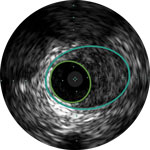

Behandlungsplan Beispiel 1

Lumen

Exzentrische fibröse Plaque mit tiefliegendem Calcium

Schallschatten

Gefässgrösse: 5,5 mm Durchmesser Plaquemorphologie: fibröse Plaque mit intimalem und mittlerem Calcium Plaquegeometrie: exzentrische Läsion Position des Führungsdrahtes: wahres Lumen

Quick-Cross-Katheter: souverän komplexe Morphologien durchqueren Direktionale Atherektomie mit Phoenix: frontal zum Schneiden, Erfassen und Freilegen gemischter Morphologien, einschliesslich Kalzium; Möglichkeit der Richtungssteuerung für grösseren Lumengewinn AngioSculpt Scoring-Ballonkatheter: Calcium messen, um eine Dissektion zu reduzieren4 Stellarex DCB: entwickelt für hohe Leistungsfähigkeit bei Kalzifizierungen